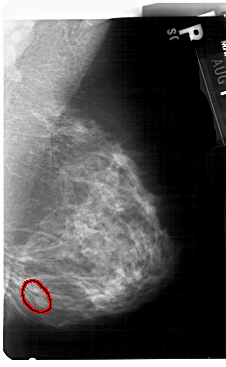

RIGHT_MLO LINES 5491 PIXELS_PER_LINE 3376 BITS_PER_PIXEL 12 RESOLUTION 43.5 OVERLAY

FILE: A_1434_1.RIGHT_MLO.OVERLAY

TOTAL_ABNORMALITIES 1

ABNORMALITY 1

LESION_TYPE MASS SHAPE OVAL MARGINS CIRCUMSCRIBED

ASSESSMENT 4

SUBTLETY 4

PATHOLOGY BENIGN

TOTAL_OUTLINES 1

BOUNDARY